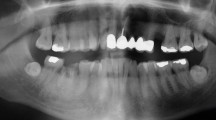

The majority would check patients’ mouths at least once daily (74.6%, n = 47) (Fig. 1). Oral conditions evaluated most commonly were: oral mucositis (98.4%, n = 62), oral ulcerations (87.3%, n = 55), oral bleeding (85.7%, n = 54), swollen gums (79.4%, n = 50), and oral pain (79.4%, n = 50). Dental caries, inflamed soft tissues, dysphagia, fungal infection, clinical abscess, dental plaque, bad breath, and oral pathology were less frequently evaluated (Details: Supplemental Table S2).